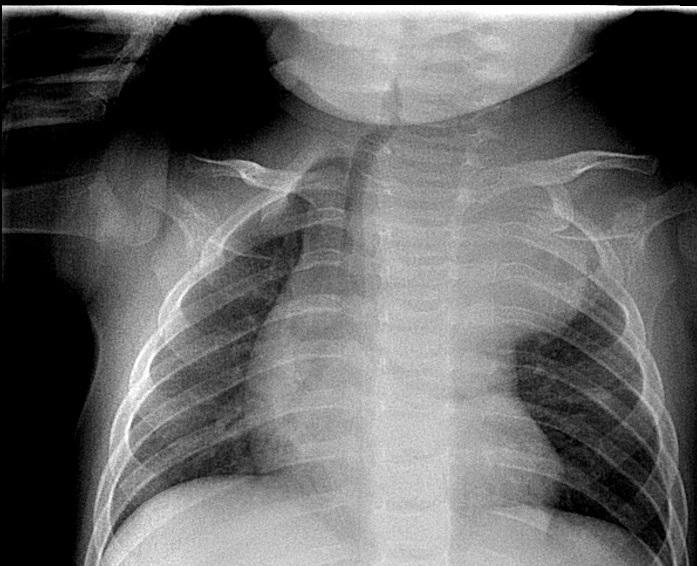

At admission to the Pediatric thoracic surgery department, the child was in a slightly poor general condition with swollen venous network of upper third of the left thoracic half, miosis of left pupil, and ptosis of left eyelid non-covering the pupil. Low grade decreased temperature of the left upper extremity with preserved peripheral pulses during the exam. Breathing was bilateral vesicular without wheeze. Laboratory tests before the surgical intervention establish leukocytosis, anemia, thrombocytosis and NSE - 163 ng/ml (reference level <17 ng/ml). Chest X-ray showed a tumor in the upper mediastinum on the left side, 4,7cm/3,2cm in size, dislocating the trachea to the right and the left main bronchus to caudal direction (Figure 2).

Figure 2. Chest X-ray showing a tumor in upper mediastinum, dislocating the trachea to the right and left main bronchus in caudal direction.